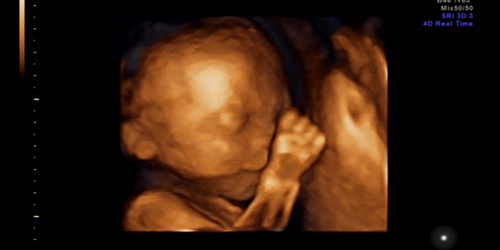

据英国《每日邮报》3月31日报道,美国马萨诸塞州一名孕妇在进行B超检查时发现胎儿摆出V字手势,该B超照片随即走红网络,引起大量转发。推特(Twitter)上也发起了“和平宝宝”的话题。有网友评论:也许孩子长大后会为世界和平作做出贡献。

四维彩超,不仅可以显示出宝宝的图像,更能够显示出宝宝的实时动态影像。

实时动态影像的呈现,不仅可以让准爸妈们看到宝宝的憨态可掬,更有助于医生发现各种异常情况。四维彩超可准确提供有关胎儿的大小、胎盘位置、羊水多少、脐带是否绕颈、脐血流是否正常等信息,还可用于测定胎儿孕龄、分析胎儿的发育情况、评价多胞胎、高危妊娠、检测胎儿异常、检测子宫的结构异常、检测胎盘异常、检测异常的出血、检测异位妊娠和其它的异常妊娠、检测卵巢肿瘤和纤维瘤、胎盘定位。

四维彩超更主要的功能就是排畸。孕妇做四维彩超需要30分钟左右的时间,因为要仔细检查头部、如唇裂,肾、心脏、脊柱裂,大脑、骨骼发育不良等是否出现异常,才能及时做好预防工作。